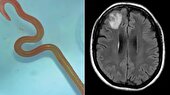

ببینید | کرم زنده در مغز!

۰۸ شهريور ۱۴۰۲ - ۱۴:۴۰ | نظر

جراحان استرالیا وقتی جمجمه زنی را شکافتند از دیدن وول خوردن یک کرم 8 سانتی متری که در غشای مغزی بیمار قرار داشت شگفت‌زده شدند.